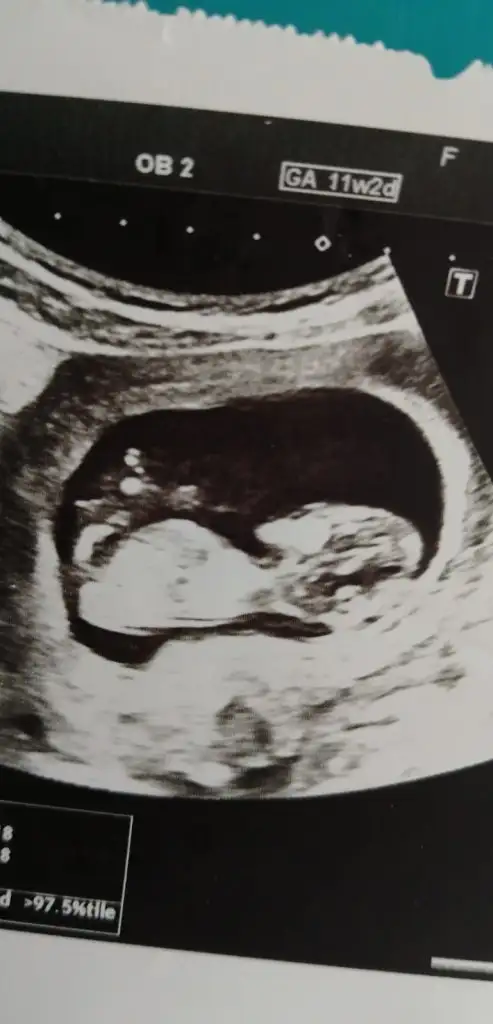

Canim 12+3 haftalık sata goreKaç haftalık usg 11 12 13 hafta olmalı sanki kız gibi

nubu görünmüyor başka usg varsa paylaşın 11 12 13 haftalar olabilirSizce kız mı erkek mi bana paralel gibi göründü Eki Görüntüle 2650002

13 haftaya yarın giriyorum doktorum 27sinde gel cinsiyet için dedi canım bakalım o gün göstermezse tekrar usg paylaşırımnubu görünmüyor başka usg varsa paylaşın 11 12 13 haftalar olabilir